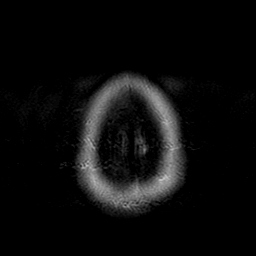

Cerebral hemorrhage, MR Study mr-t2 -- Slice #23

[Home][Help][Clinical] Slice 23